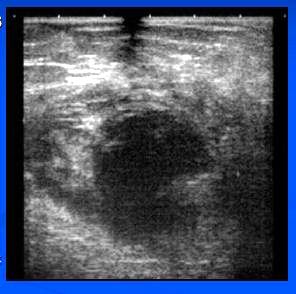

- UZ – heterogenní, izo a hypoechogenní, ostře ohraničené ložisko

- Dg. – intracyst.tumor?

- HI: Epidermoidní cysta